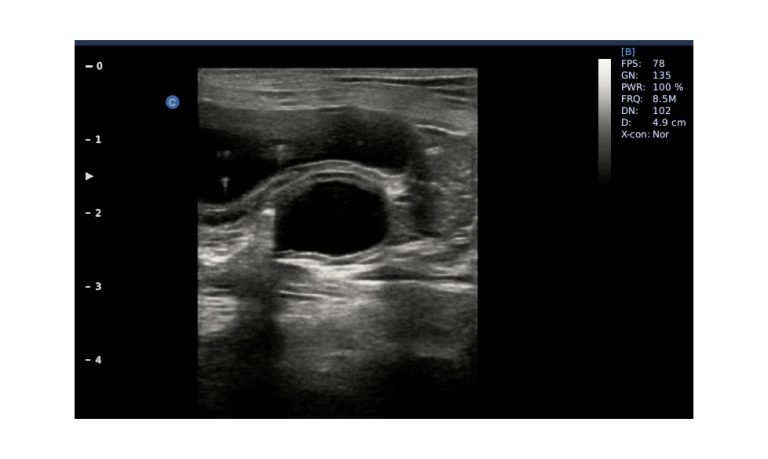

Ultrasound

Wide range of Ultrasound machines that suites a variety of applications from abdominal to rectal scans, we take in consideration how the world is moving towards mobility and mobile applications.

SonoScape Pro Pet E11

Smart Imaging

Introducing the first portable ultrasound with the C-Field+TM platform, redefining diagnostic imaging. Designed for veterinarians, it delivers unmatched clarity, ultra-fast processing, and seamless adaptability for all species. Experience Smart Imaging, Heartfelt Care—anywhere.

Equipped with cutting-edge veterinary software and optimized workflows, it embodies our commitment to Smart Imaging, Heartfelt Care – Wherever Their Journey Leads, with unparalleled performance and adaptability, this innovative system empowers veterinarians to provide exceptional care across all diagnostic applications,

Esaote MyLab Sigma; So Fast, So Easy

Esaote’s new MyLab™SigmaVET is the smart, portable solution that allows use of an ultrasound whenever a quick and complete diagnosis is required.

EBIT50/60 VET

All the power you need

The EBit provides all the power you need for today´s challenging clinical environment, yet remain ultra-portable, ultra-affordable. With its cutting-edge imaging technologies, precise and intuitive workflow, ergonomic and eco-friendly design, versatile transducers for all applications from top to toe, we firmly believe the EBit to be the very best portable ultrasound in its class today.

ECO5 VET

Ultra-Portable, Ultra- Affordable, Color doppler

The multi-purpose user presets, comprehensive measurement & report system, built-in EasyView image achieve system, quick image storage / retrieve / transfer, one-button direct print, make the complete workflow better than what you can dream of.